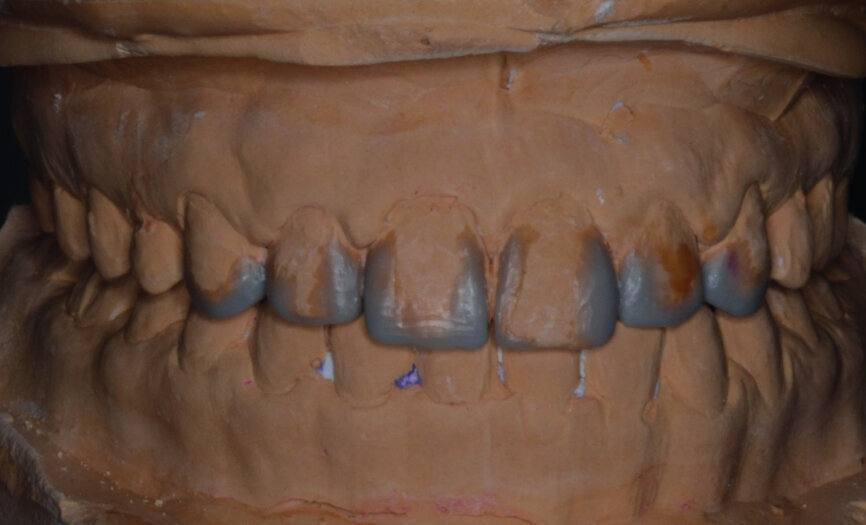

At the end of orthodontic treatment, gingival margins were well aligned, midlines were centred and canines and first premolars were positioned to facilitate the restorative phase of treatment (Figs. 34–36). At this phase, a final CR mounting and wax-up was performed (Figs. 37–39), as well as the anterior teeth restorations (Fig. 40).

Orthodontic treatment has improved both dental and facial aesthetics (Figs. 41–47) and the functionality of the occlusion (Figs. 48–52).